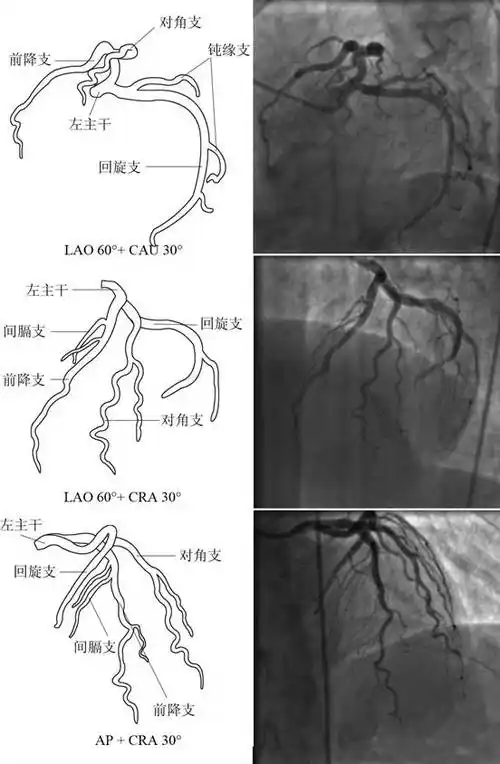

冠状动脉造影